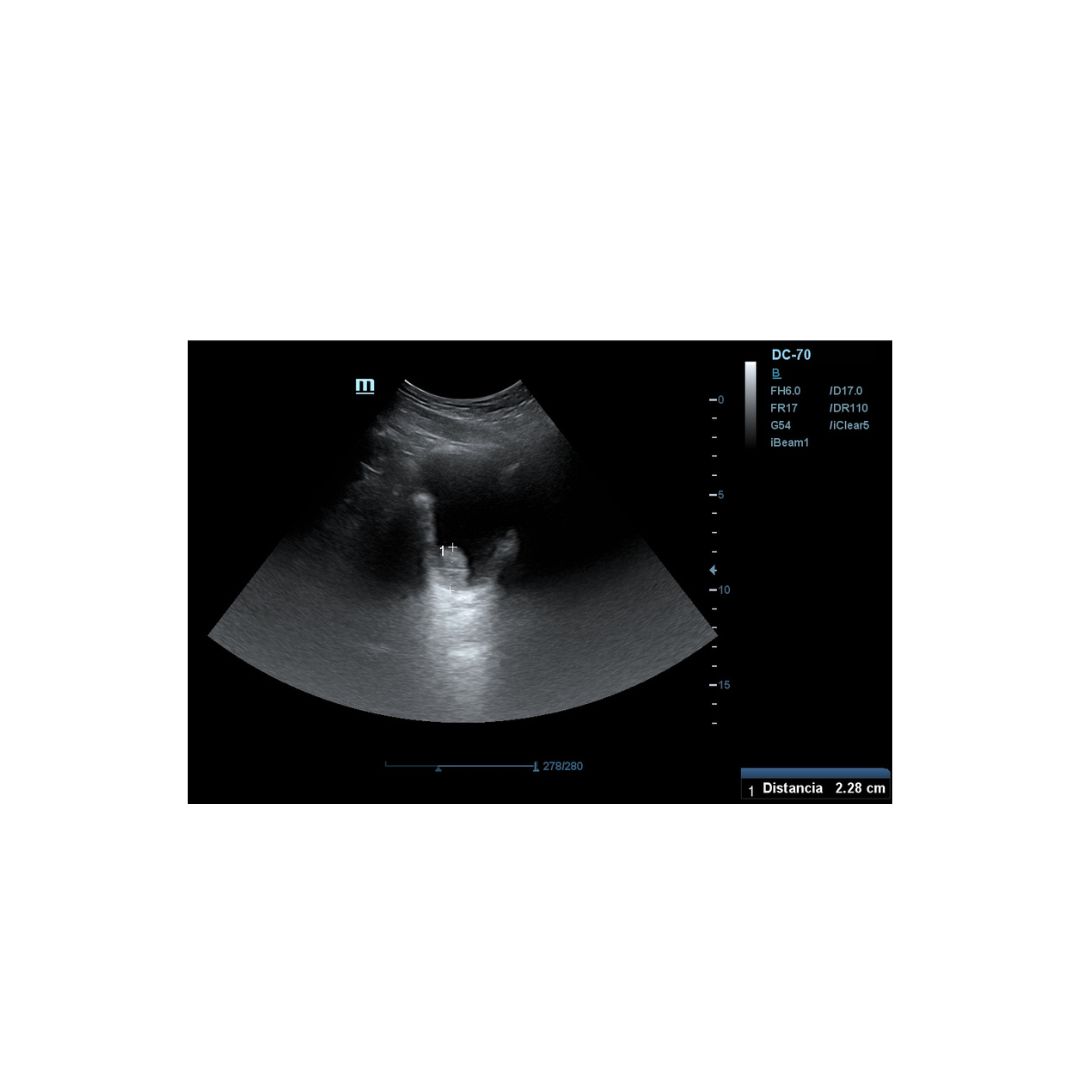

Es derivado a consulta de ecografía de nuestro centro de salud, donde realizamos Ecografía clinica abdominal, apreciándose imagen hiperecogénica pediculada en pared posterior izquierda de la vejiga vejiga, fija, que mide 2,26 mm aproximadamente en su eje mayor, sin captación Doppler.